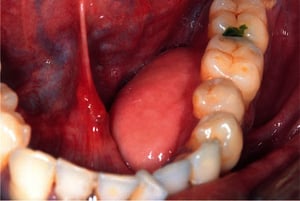

Dieses Foto zeigt eine Nahaufnahme einer Ranula (Mitte) im Mund einer Person. Ranulas sind Mukozelen, die im Mundboden auftreten (im Allgemeinen größer als Mukozelen, die an anderen Stellen in der Mundhöhle auftreten). Die Quelle des Muzingehalts in Ranulas ist in der Regel die sublinguale Drüse (gelegentlich auch der submandibuläre Drüsengang).

Mukozelen (Schleimretentionszysten und Ranulas) sind schmerzlose, gutartige intraorale Schwellungen aufgrund zystischer oder pseudozystischer Ansammlungen von Speicheldrüsenschleim. Sie sind oft traumatischen Ursprungs. Bei weitem die häufigste Läsion, Mukozelen, treten am häufigsten in der lateralen Unterlippe auf und haben oft eine bläulich durchscheinende Farbe aufgrund des Auftretens von verschüttetem Mucin unter der Mukosa. Sie sind in der Regel die Folge versehentlichen Beißens der (unteren) Lippe und tritt auf, wenn Speichel, der aus der kleinen Speicheldrüse in den Mund fließt, blockiert wird. Die meisten Mukozelen verschwinden in einer oder zwei Wochen. Ranulas sind große, meist bläuliche Mukozelen am Boden des Mundes. Die Behandlung ist eine chirurgische Exzision.